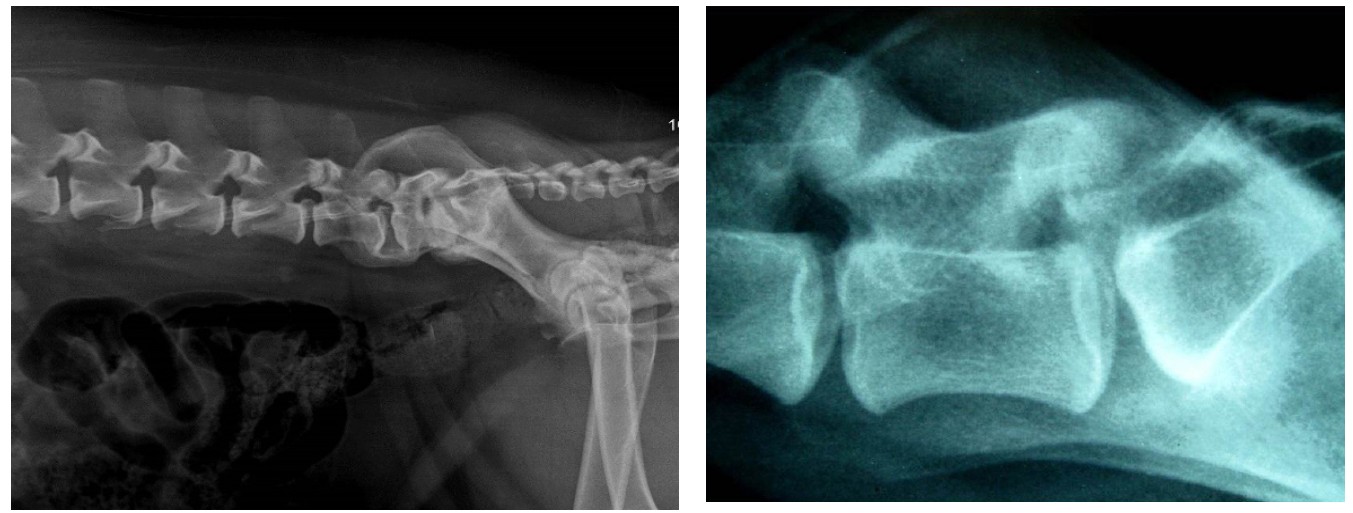

Fig. 1. Radiograph of the dog’s vertebral column in lateromedial projection on the right side: narrowing of the intervertebral space between the bodies of vertebrae L7-S1, ventral spondylosis of L6-L7-S1, sclerosis of the end plates of caudal pole of L6—7 and cranial pole of S1, ventral displacement of S1—3

Source: created by S.A. Yagnikov, L.S. Barsegyan